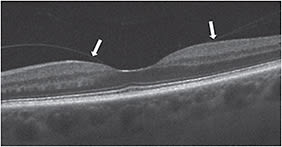

Lamellar holes or partial-thickness macular holes can appear similar to full-thickness macular holes on slit lamp biomicroscopy. OCT imaging of lamellar holes may show an irregular foveal contour or loss of the inner retina, or both, but an intact photoreceptor layer is always present (Figure 4). FTMHs are defined as an absence of all retinal layers in the foveal region (Figure 5, page 40). They can be small (250 µm or smaller), medium (250 µm to 400 µm) or large (400 µm or larger).

Figure 4: This lamellar hole without VMA shows an abnormal foveal contour, but an intact photo-receptor layer.